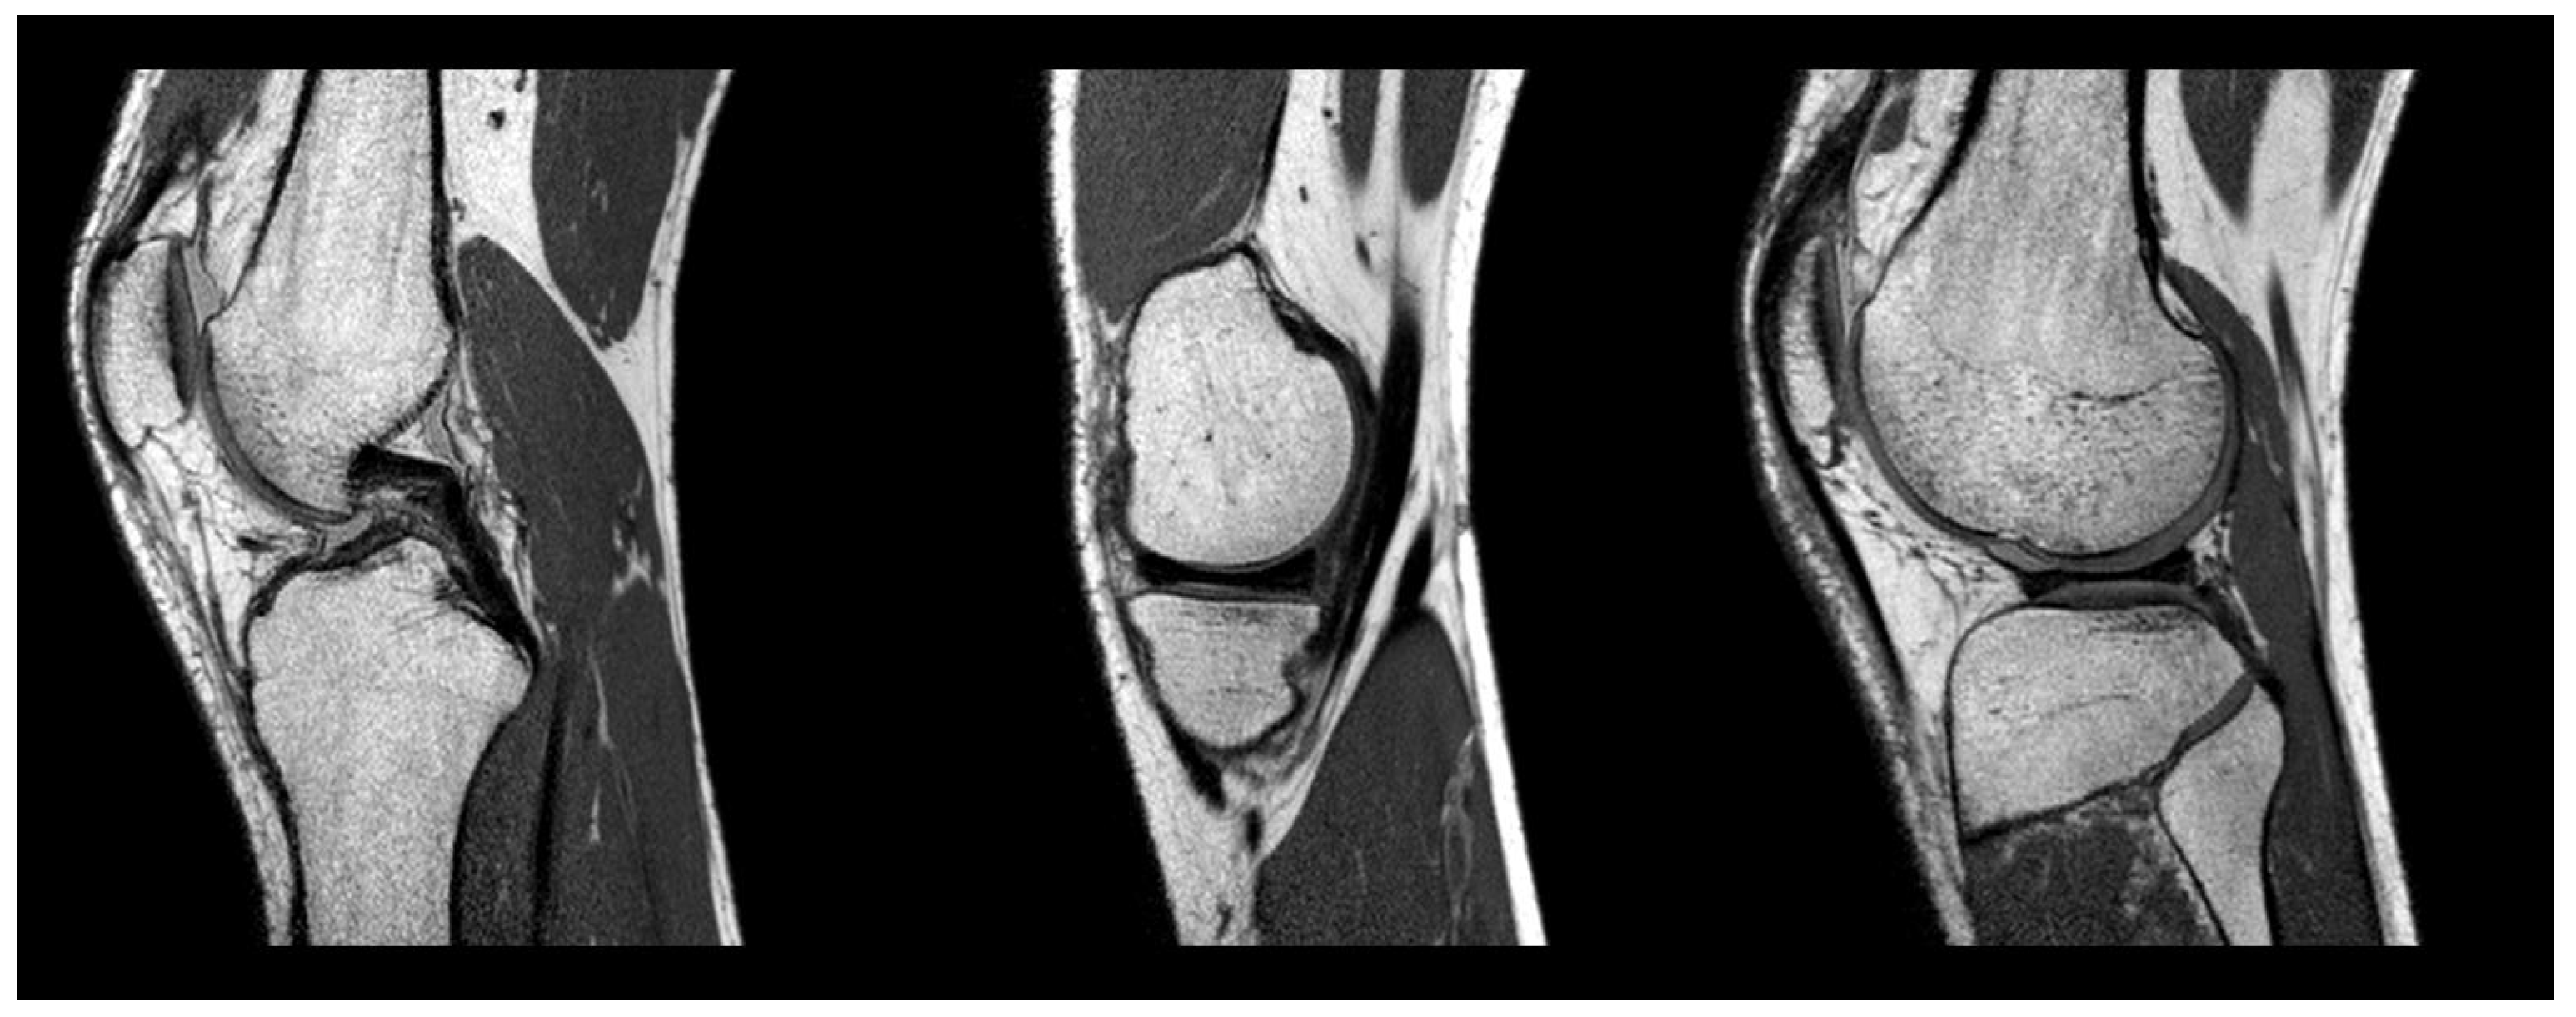

| Original Image | Ground Truth | U-Net | Attention U-Net | Our Approach |

|---|---|---|---|---|

![]() | ![]() | ![]() | ![]() | ![]() |